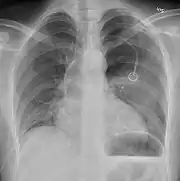

Radiografía

Una radiografía realizada en proyección postero-anterior (de atrás hacia delante) y durante la inspiración máxima constituye la forma de diagnóstico más frecuente.[38] Las imágenes realizadas en espiración, al contrario, no poseen valor diagnóstico significativo,[20] aunque pueden resultar útiles cuando existe una alta sospecha de neumotórax pero la radiografía en inspiración aparece normal.[39] Si este es el caso, también pueden realizarse radiografías de proyección lateral, aunque esta práctica no se realiza con frecuencia.[20][31]

radiografía anteroposterior que muestra un neumotórax de reducido tamaño en el pulmón izquierdo, causado por una punción

A veces puede darse una desviación del mediastino hacia el lado contrario en el que se halla el neumotórax debido a las diferencias de presión que crea esta patología. La presencia de esta desviación no implica la existencia de un neumotórax a tensión, que habitualmente se diagnostica a través de signos de gravedad como hipoxia severa y choque obstructivo.[30]

El tamaño del neumotórax (es decir, la cantidad que este ocupa en la cavidad pleural) puede determinarse midiendo la distancia entre la caja torácica y el borde del pulmón. Esto es de relevancia para el tratamiento, ya que los neumotórax de menor tamaño a menudo poseen un enfoque terapéutico distinto. Una distancia de dos centímetros significa que el neumotórax ocupa un 50 % del hemitórax.[20] Las guías de práctica clínica afirman que esta medida debe darse a partir del hilio pulmonar, con un umbral de referencia de dos centímetros para indicar la presencia de un neumotórax de menor o mayor tamaño. La medida también puede realizarse a partir del ápice pulmonar, y en este caso el umbral es de tres centímetros,[40] aunque esta forma de medición puede hacer pensar que el tamaño del neumotórax es mayor si este se encuentra concentrado en la parte superior de la caja torácica.[20][31] Aun teniendo en cuenta esto, estos métodos de medida no poseen una correlación perfecta con el tamaño del neumotórax y, aunque el TAC ofrece imágenes más precisas en este sentido, se desaconseja su uso en estas situaciones clínicas.[20]

No todos los neumotórax son uniformes; algunos ocupan solamente un pequeño espacio en un espacio particular de la cavidad pleural.[20] A veces, pueden hallarse pequeñas cantidades de líquido en la radiografía (hidroneumotórax), que puede estar constituido por sangre (hemoneumotórax).[30] En algunos casos la única manifestación de estos que se da en la radiografía es el signo del surco profundo, por el cual se da un aumento del espacio entre la caja torácica y el diafragma por la presencia de líquido.[35]